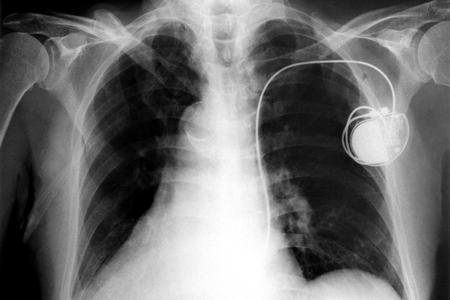

Stimulateur cardiaque (Pacemaker)

Une autre invention qui a sauvé et sauve encore de nombreuses vies : l’implantation de la pile cardiaque. Alors que le premier pacemaker fait son apparition à la fin du XIXème siècle, ce n’est qu’en 1958 qu’il est totalement possible d’en implanter un à l’intérieur du corps humain, grâce aux savoirs de l’ingénieur Rune Elmqvist et du chirurgien Åke Senning. L’expérience se fera la toute première fois le 8 octobre dans l’hôpital universitaire de Karolinska près de Stockholm, sur le patient Arne Larsson qui aura vécu jusqu’à 86 ans grâce à son pacemaker.